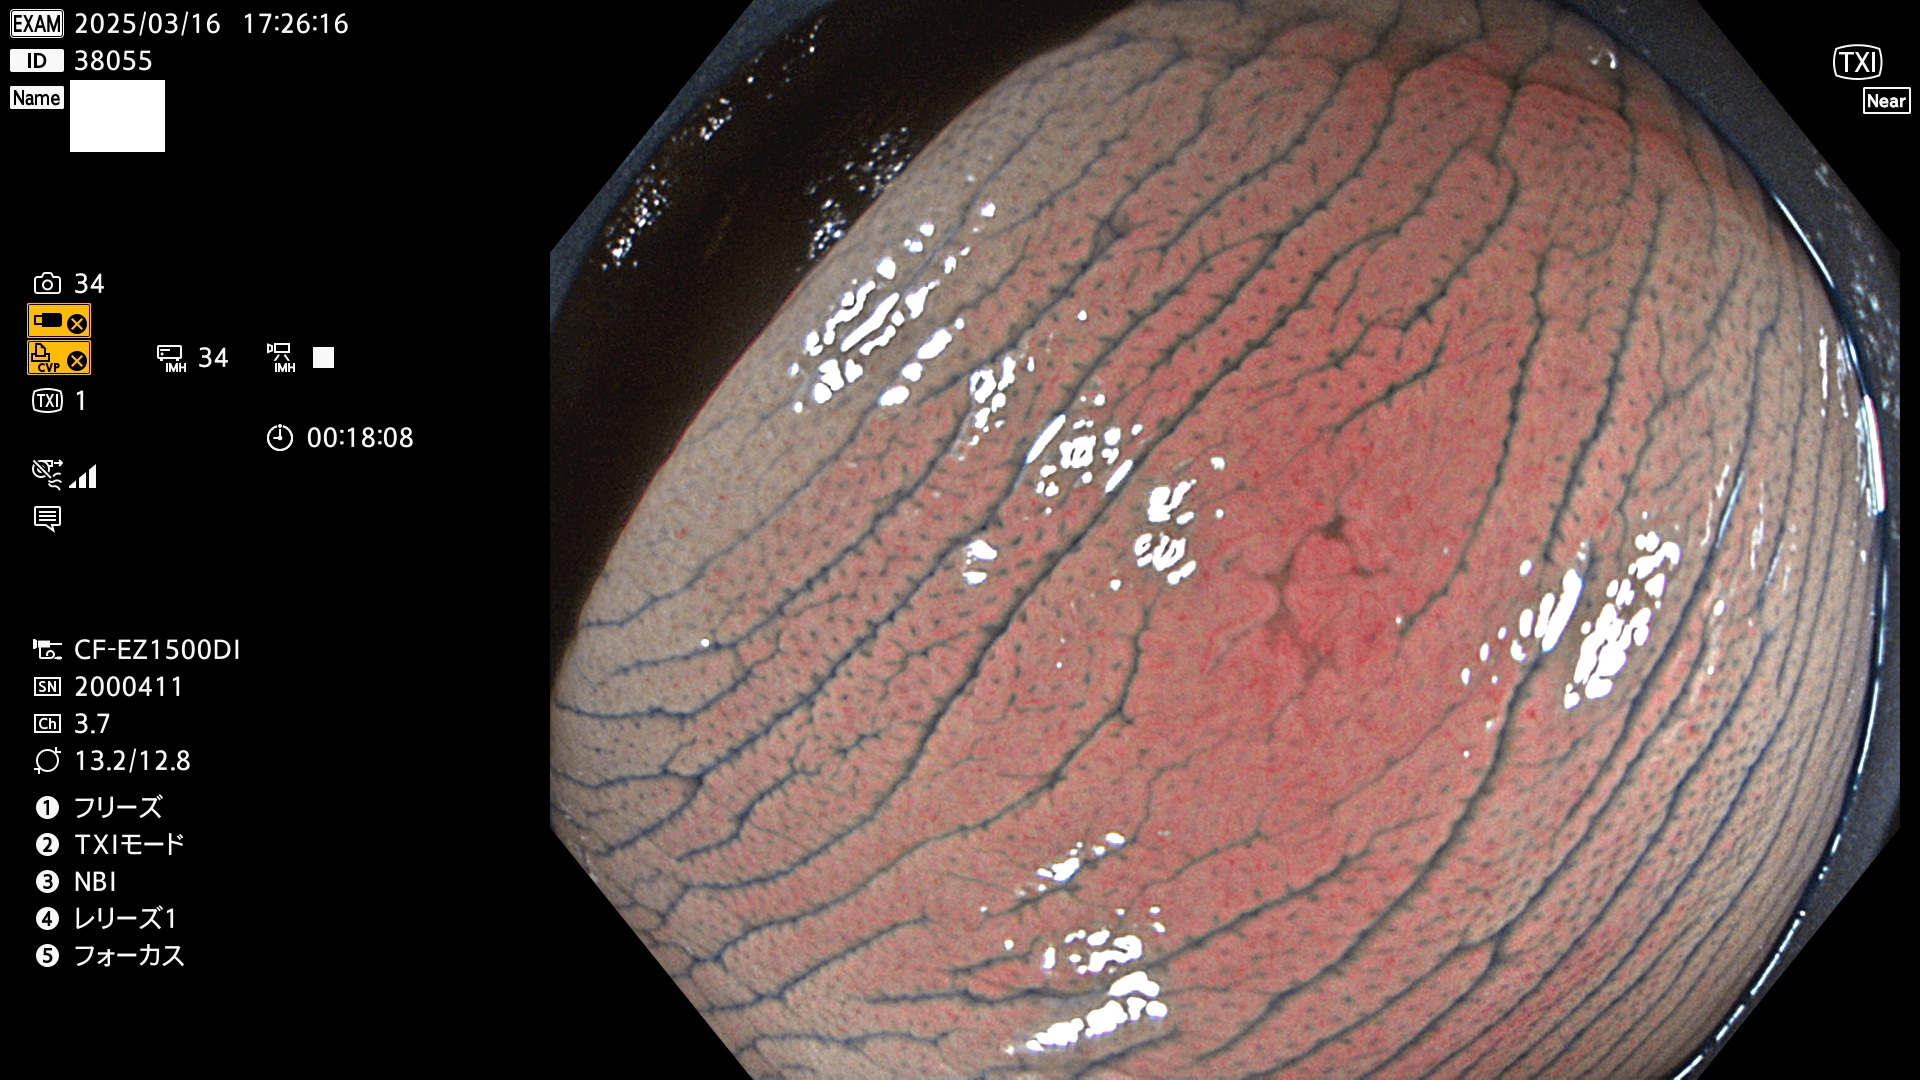

今週のUb、Uc型腺腫

完全に平坦な物をUb、陥凹している物をUcと呼びます。最も発見が難しく危険な病変です。

毎週の検査(木・金・土・日)に発見されたUb、Uc型・腺腫を、その週の日曜の夜にUPし1週間、提示します。

抽出の対象期間 2025年3月13日〜3月16日の4日間(48件の検査)12個 (12/48=25%)